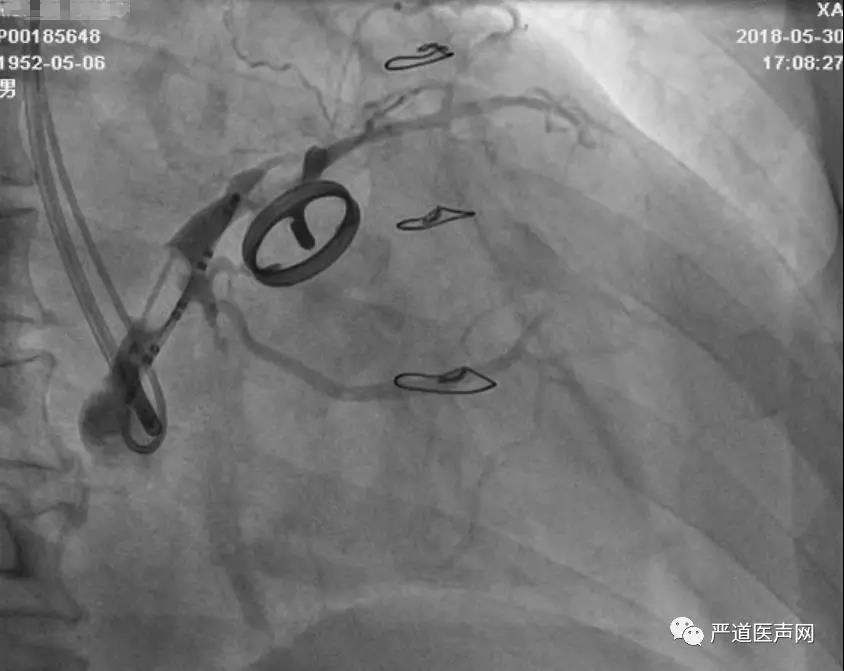

病例:

66岁男性患者,2000年因气短,发现心脏杂音,诊断为主动脉瓣狭窄并关闭不全,行主动脉瓣机械瓣置换术,后因反复气喘20余年,加重半年于2018年5月入院。心脏彩超示:LVEDd 69mm,LAd 44mm,RVd 30mm,LVEF 23%,主动脉瓣机械瓣置换术后功能良好,二尖瓣、三尖瓣少量反流。心电图示窦律,完全性左束支阻滞,QRS 210ms,监测示频发室早,短阵室速。手术要点:送入冠状窦十极电极,作为路标,鞘管在红靶消融电极指引下进入冠状窦。通过组合图像找到靶血管,导丝锚定于心中静脉,加强系统支撑力,撤出Pilot50导丝,保留微导管,更换为300cm BMW导丝,随后植入左室电极。

27.jpg

28.jpg

29.jpg